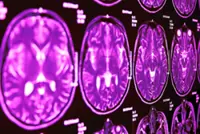

IPOH: The unexpected death of a popular Malaysian artist at a young age has brought attention to a medical condition known as a brain aneurysm.